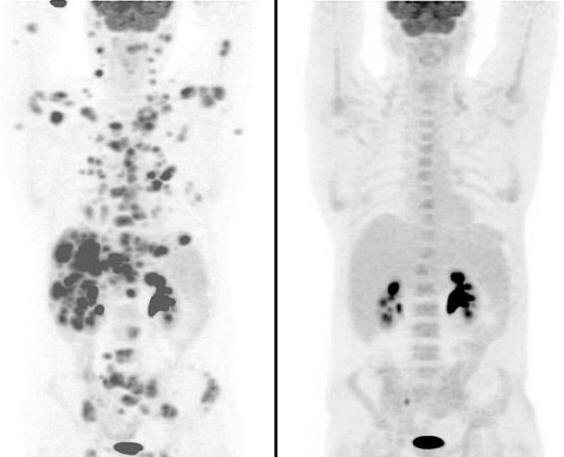

Човек, страдащ от рядка и агресивна форма на рак Великобритания Ян Брукс, чието тяло беше ударено от около 70 години злокачествени тумори, според най-оптимистичните прогнози на лекарите останаха само няколко седмици. Лекарите признаха това изпробвах почти всички възможности за лечение. Въпреки това, въпреки разочароващи прогнози, в момента 47-годишният Брукс е в пълна ремисия, след като е първият човек, който е опитал ново лекарство против рак. за снимките показват колко рак се е разпространил в цялото тяло на човека. Второ сканиране обаче, направено само за няколко седмици след приема на новото лекарство той показа невероятно подобрение. Снимки, направени преди и след лечението

Снимки от открити източници Всички тумори бяха унищожени. Единствените тъмни петна, видими на снимките, показват нормално функциониране на бъбреците и пикочния мехур. клиничен тест в болница Кристи в Манчестър се оказа така Успешно, че лекарството, беше решено да се опита на други пациенти. Сега пациенти със същата рядка форма на неходжкинов лимфом – вид рак, който засяга и лимфните възли ще получи лекарството. „Не мисля, че днес щях да съм тук от това лекарство. Лекарят ми беше толкова развълнуван, когато видя резултати, които веднага ми ги показаха. Имах 70 тумори и всички те изчезнаха “, каза Брукс в интервю за Mail Online, Автомобилен механик от Болтън. Мъжът имал рядка форма на рак, която наречен анапластичен голям клетъчен неходжкин лимфом. Заболяването му е диагностицирано през 2001 година и в началото реагира добре на лечението, но през 2008 г. – върна се. Човек се подлага на трансплантация на стволови клетки, но рак се върна отново, като започна да се разпространява бързо. Като се има предвид, че от лекарите смятаха, че му остава само няколко седмици да живее, Брукс реши да участва в клинични изпитвания. Състояние на пациента започна да се подобрява в рамките на първите 24 часа след стартирането наркотиците и лекарите на най-големия раков център в Европа бяха ударени, след като видя резултатите от сканирането. След само 12 седмици лечение онколозите установили, че тялото му напълно се е отървало от тумори. Според тях Брукс в момента е в пълно състояние ремисия.